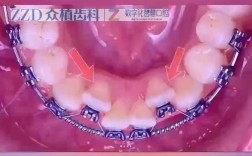

传统金属托槽矫正:这种方式的“痛苦”主要来自托槽对口腔黏膜的摩擦,初期容易磨破嘴唇、脸颊,引发口腔溃疡,不过医生通常会提供正畸蜡,将托槽包裹起来就能缓解,金属托槽的力度相对直接,初期酸胀感可能稍明显,但适应期也短。

陶瓷托槽矫正:陶瓷托槽的颜色更接近牙齿,美观度更高,但材质比金属硬,初期摩擦黏膜的可能性更大,且部分陶瓷托槽的边缘可能更粗糙,需要更注意口腔护理,疼痛感与金属托槽类似,主要是酸胀和摩擦不适。

舌侧矫正:托槽粘在牙齿内侧,隐蔽性好,但初期对发音的影响最大(可能说话大舌头),且内侧黏膜更容易被托槽摩擦,疼痛和不适感比传统矫正更明显,适应期也更长(通常1-2周),不过舌侧矫正的力度更精准,移动效率高,适合对美观要求极高的人。